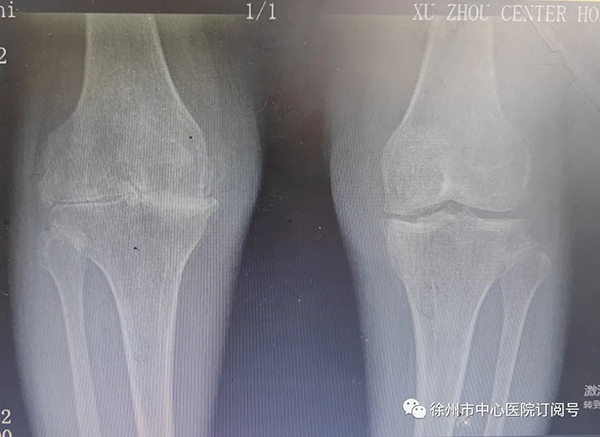

最終,那鍵團(tuán)隊(duì)結(jié)合影像資料,患者癥狀,實(shí)驗(yàn)室檢查等決定對(duì)潘女士施行右膝全部膝關(guān)節(jié)置換術(shù)。

(手術(shù)前后影像對(duì)比)

術(shù)中,發(fā)現(xiàn)患者股骨、脛骨、髕骨軟骨廣泛剝脫,髕骨關(guān)節(jié)軟骨下骨裸露,邊緣有大量骨贅形成,內(nèi)外側(cè)半月板退變,邊緣毛糙,關(guān)節(jié)腔內(nèi)可見(jiàn)大量淡黃色滑液,滑膜增生肥厚。那鍵憑借豐富的臨床經(jīng)驗(yàn),將患者右膝關(guān)節(jié)全部置換,手術(shù)順利完成。